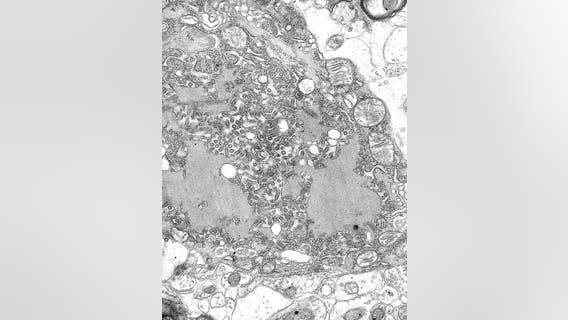

Teen who received life-saving transplant reacts to medical breakthroughs using pig organs

A human donor saved the life of 15-year-old Wilfre Mercedes. Today, after doctors successfully transplanted a pig's heart into a human patient, Mercedes is hopeful thousands of others on transplant waiting lists can go on living, just like he did.